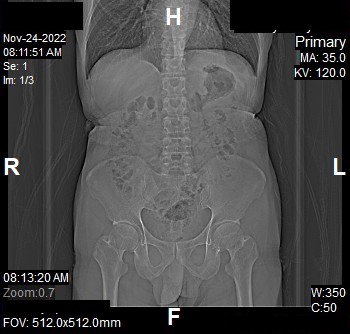

Topogram

- Position the patient in head first supine position.

- Align the patient in Mid-Sagittal plane of the table.

- Position the transverse laser light beam at the level of patient’s nipple line to start the topogram.

Topogram Parameters

- Topogram length: 512 mm

- Slice: 0.6 mm

- Scanning direction: Craniocoudal

- Tube position: Top

- Stop the topogram scanning when the scanning reach / pass over the inferior ischial ramus.